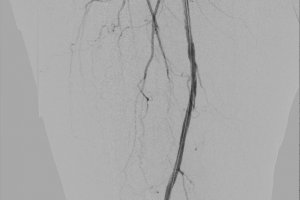

Одной из успешно выполненных эндоваскулярных операций была баллонная ангиопластика рестеноза (повторного сужения) бедренной артерии. Пациенту уже выполнялась подобная процедура полгода назад по месту жительства в связи с болью в мышцах нижних конечностей при ходьбе на расстоянии 100–200 метров. После первой операции боль прошла, однако она возобновились вновь через 7 месяцев. Осмотр и исследования позволили выявить критический рестеноз оперированной артерии.

Нашими хирургами выполнена уникальная операция на «заросшей» артерии с помощью баллонного катетера с лекарственным покрытием, показавшим свою эффективность в значительном удлинении сроков повторного стеноза артерии.

Следует отметить, что благодаря своевременно выявленной проблеме, вся операция проводилась через один прокол в паховой области, без разрезов, без наркоза (с применением местной анестезии) и длительностью всего 50 минут. Уже на следующий день пациент вновь мог свободно ходить без боли в ноге длинные дистанции.